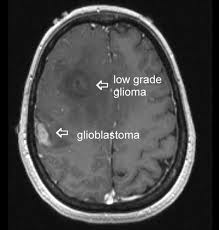

Información: El glioma es un tipo de neoplasia que se produce en el cerebro o en la médula espinal. Se llama glioma, ya que surge a partir de células gliales. Su ubicación más frecuente es el cerebro.1

Los gliomas son clasificados por tipo de células, por grado, y por ubicación.

Por grado

De bajo grado son gliomas bien diferenciados (no anaplásico); estos son benignos y auguran un mejor pronóstico para el paciente.

De alto grado son gliomas indiferenciados o anaplásicos; estos son malignos y tienen un peor pronóstico.

Actualmente los exámenes de elección en el diagnóstico spn la TC y la Resonancia Magnética (RM). La imagen característica en la TC es de un área hipodensa de tamaño variable, generalmente bien circunscrita, que no toma contraste. Algún grado de débil impregnación se describe en hasta el 50%. Sin embargo cuando un astrocitoma de bajo grado toma mucho contraste, se debe sospechar malignización. Las calcificaciones son frecuentes en los oligodendrogliomas y raros en los astrocitomas.

La RM, es un examen de gran valor en gliomas de bajo grado pues a menudo demuestra lesiones no detectables con la TC.